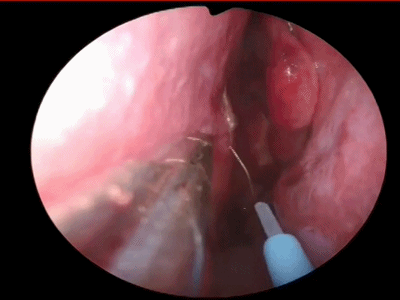

▼鼻中隔黏膜 切口的位置:可根据鼻中隔的弯曲情况,一般应于鼻中隔的凸面进入,利于分离。在皮肤与黏膜交界处切开,靠近皮肤以避免撕破黏膜,即Killian切口。

![]()

▼本文展示两种切开方式:①单极切开;②小圆刀切开。

下图示使用单极在右侧 Killian切口处上下方向划开鼻中隔粘膜。